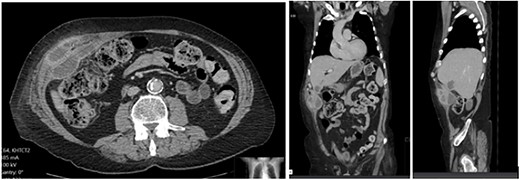

A 65-year-old gentleman with a body mass index of 29.6 and medical history of Guillain–Barré syndrome, type 2 diabetes mellitus, hypertension, and chronic pain was referred to our outpatient clinic with intermittent upper abdominal pain. His surgical history included an open appendicectomy. He was wheelchair-bound outside his home and received weekly assistance from a carer. On examination he was anicteric. His abdomen was soft, but a mildly tender mass was palpable in the right upper quadrant. An initial computed tomography (CT) scan showed thickening of the gallbladder and a collection extending from the fundus and infiltrating the anterior abdominal wall (Fig. 1). Further scans showed extension of the collection towards the midline (Fig. 2). He subsequently presented to the emergency department with purulent discharge from an external orifice adjacent to the umbilicus. An ultrasound-guided 6Fr pigtail drain was then placed into the known abdominal wall collection.

CT abdomen with portal venous contrast in axial plane showing extension of collection towards the paraumbilical region.